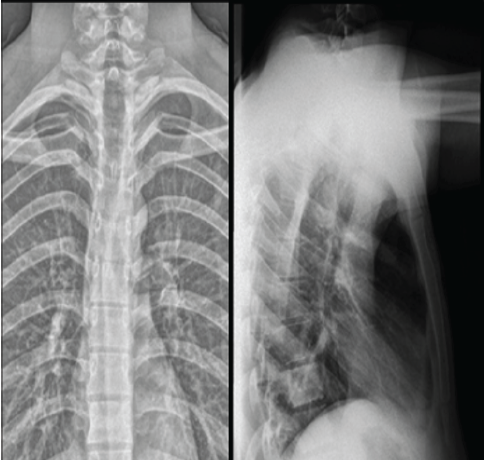

Neurological improvement was observed soon after decompression surgery. At 6 weeks post-operatively, motor strength had improved to 4+/5 in most key lower limb muscle groups with regained bladder continence, corresponding to ASIA Grade D (Fig. 3). This functional recovery underscores the importance of early surgical decompression in patients presenting with acute metastatic cord compression.

Figure 3: Six-week post-operative radiographs (anteroposterior and lateral views) showing maintained spinal alignment and stable post-operative changes at the D1–D2 level with satisfactory decompression and no evidence of progression of disease.